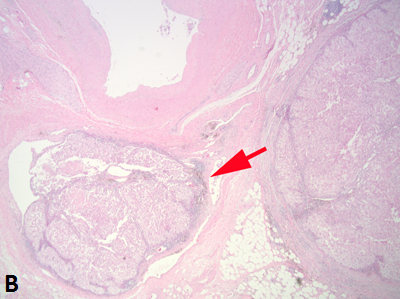

Figure 1B

Sinus fat invasion occurs when intravenous tumor invades through the media (33), however, in some cases tumor bulging into the sinus can be difficult to interpret. Recommendations for sampling have varied with protocols ranging from sampling of the entire interface to 2-3 blocks (6, 7, 34, 35). At the meeting there was consensus that when invasion of the renal sinus is uncertain, at least three blocks of the interface should be taken. If invasion is grossly evident or obviously not present (small peripheral tumor) only 1 block is needed to confirm the gross impression.

Figure 1B. Tumor grossly involving the renal vein is usually visible to the naked eye. A tumor thrombus typically expands the renal vein. The renal vein margin (arrow) often retracts back from the tumor thrombus when vein clamps are removed.